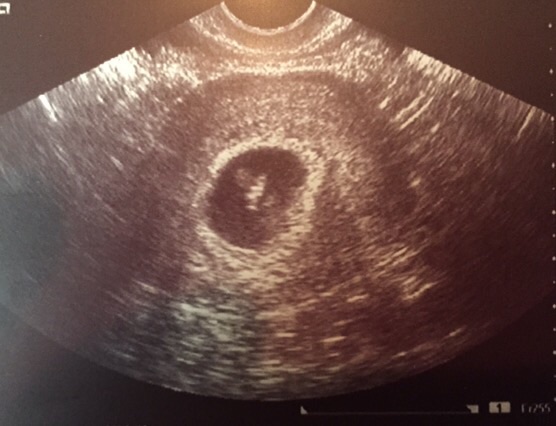

Our first appt was today! I was so nervous after 18 mths of infertility and a miscarriage in October - but baby is healthy and growing right on track! 7 weeks, 4 days, 168bpm!! So exciting!!